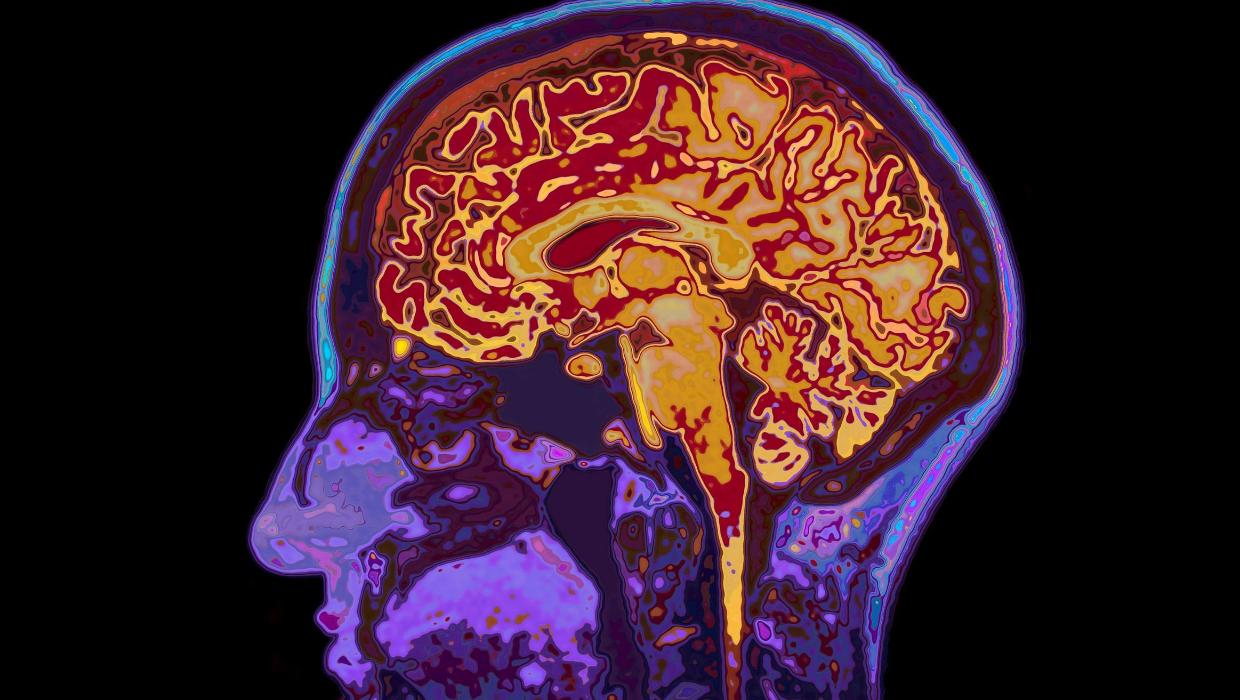

Research conducted by the University of Cambridge has unveiled new insights into human brain development, suggesting that the brain remains in a state of adolescence until the age of 32. This study identifies five significant epochs of brain maturation, marking four critical turning points throughout an individual’s life.

The findings, published in March 2024, reshape our understanding of cognitive development. The research outlines a timeline of brain evolution, highlighting that significant changes occur not only during childhood and adolescence but also in early adulthood. This challenges the long-held belief that brain development is largely complete by the late teenage years.

According to the study, the first epoch occurs during early childhood, where foundational cognitive abilities begin to form. The second phase, spanning from ages approximately 7 to 11, is characterized by enhanced language and social skills. The third epoch extends from ages 12 to 18, coinciding with adolescence, when emotional regulation and decision-making capabilities are notably refined.

The research emphasizes the fourth epoch, which continues from ages 19 to 32. During this period, individuals experience profound changes in their brain structure and connectivity. This stage is crucial for developing complex reasoning and social interactions, illustrating that brain maturation is an ongoing process well into early adulthood.

The final epoch begins at age 66, marking the onset of cognitive decline as the brain starts to age. This shift may lead to slower processing speeds and memory challenges, underscoring the importance of cognitive health as individuals progress through their later years.